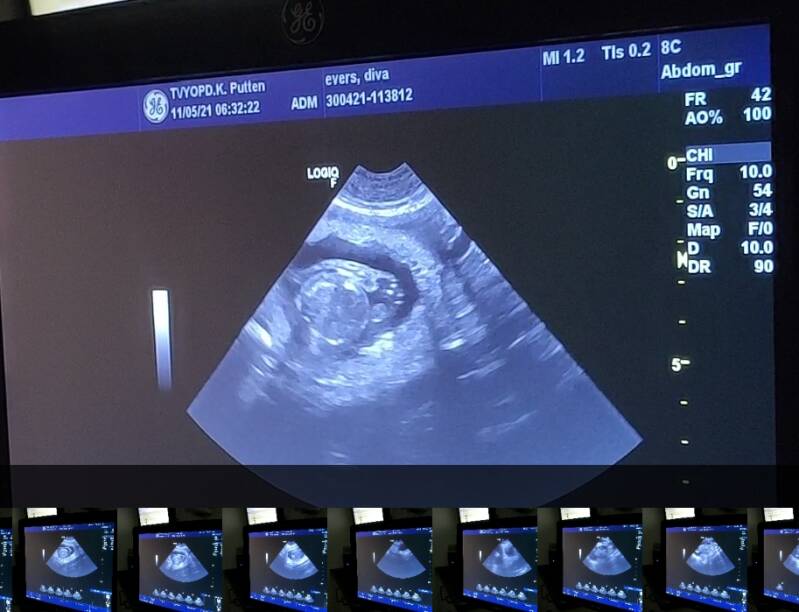

Yora is drachtig!!! 5-3-21

Vanmorgen hadden we een drachtecho in de dierenkliniek Putten. Goed nieuws! Er waren zeker 7 vruchtjes te tellen.. (kunnen er meer zijn) Ze waren nog wat aan de kleine kant dus vermoedelijk is ze pas na de tweede dekking bevrucht. Haar pups kunnen we dus rond 10/12april verwachten.